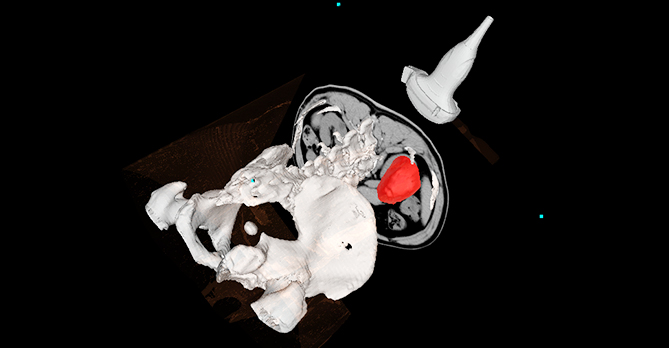

基于AI配准的多模态影像2D-3D联动

更精准的实时呈现病灶位置

AI辅助针尖动态识别

精准引导建立手术通道